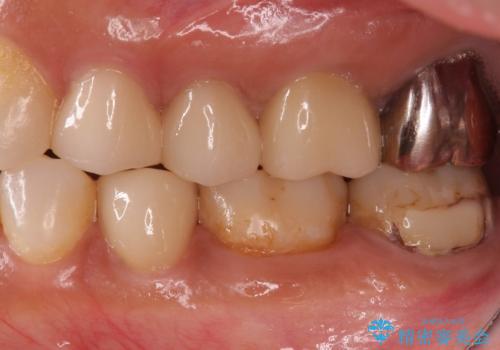

- 左下7 仮歯+e-maxクラウン:11,000円+77,000円費用は治療当時の料金となります

今回の場合、虫歯の大きさが大きく本来であれば歯茎に対しても治療をすることが検討されケースですが、ご希望されなかったため被せ物のみでの治療となりました。

出産前後では口腔内環境が変わることが多々あります。

是非落ち着いたタイミングで検査を受けることをお勧めします。